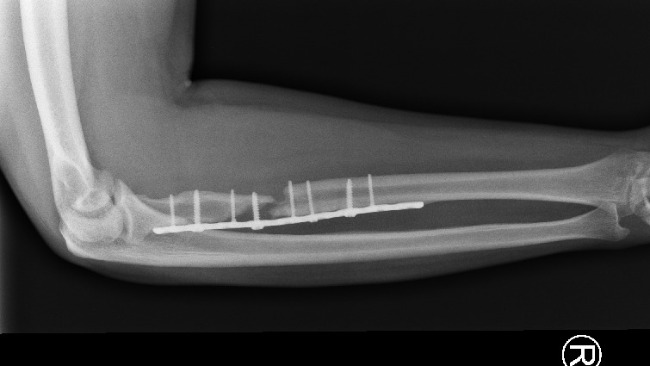

Ponad rok w matni bólu i upokorzenia. Ta jedna „zwykła” operacja spowodowała, że moja kość stale obumierała powodując 3 cm ubytku w kości co widać na RTG przedstawiającym rękę na luty 2025 już po dwóch operacjach (zepsuta w ZCO DG i naprawiająca w Szpitalu Miejskim w Sosnowcu. Do 29.01.2026, przez ostatnie półtora roku przeszedłem poważne 3 operacje stabilizacji kości, w tym jedną z przeszczepem kości z biodra do ręki oraz 1 zabieg biopsyjny - dodatkowe wiercenie drugiego biodra i bolesne ostrzykiwanie szpikiem biopsyjnym, serii ostrzyknięć komórkami wzrostowymi, niekończącą się rehabilitację i zabiegi, przy których ból do prowadzał do utraty przytomności. Co tydzień jestem podpinany pod bardzo nieprzyjemny prąd aby naprawić porażony nerw. Miałem być oparciem dla bliskich, a stałem się człowiekiem, którego partnerka musi myć gąbką na stołku, bo sam nie jest wstanie ustać z bólu, oraz pomagać mi w codziennej egzystencji. To upodlenie, którego nie życzę nikomu, zwłaszcza gdy masz całe życie przed sobą. Miałem być oparciem a stałem się ciężarem, którego sam nie mogę unieść..

Ostatni dzwonek. Mimo mojej walki, diagnoza ze stycznia 2026 roku zwaliła mnie z nóg: staw rzekomy, brak zrostu. Lokalni lekarze sugerują skrócenie ręki o 3 cm i "nauczenie się życia z kalectwem". To również powoduje potencjalną szansę na nie zrost kostny. Jestem po 3 operacjach w tym jednej z przeszczepem kości z biodra i 1 zabiegu wiercenia biodra i ostrzyknięciu szpikiem kostnym. Na horyzoncie kolejna operacja a mam obecnie dopiero 24 lata..